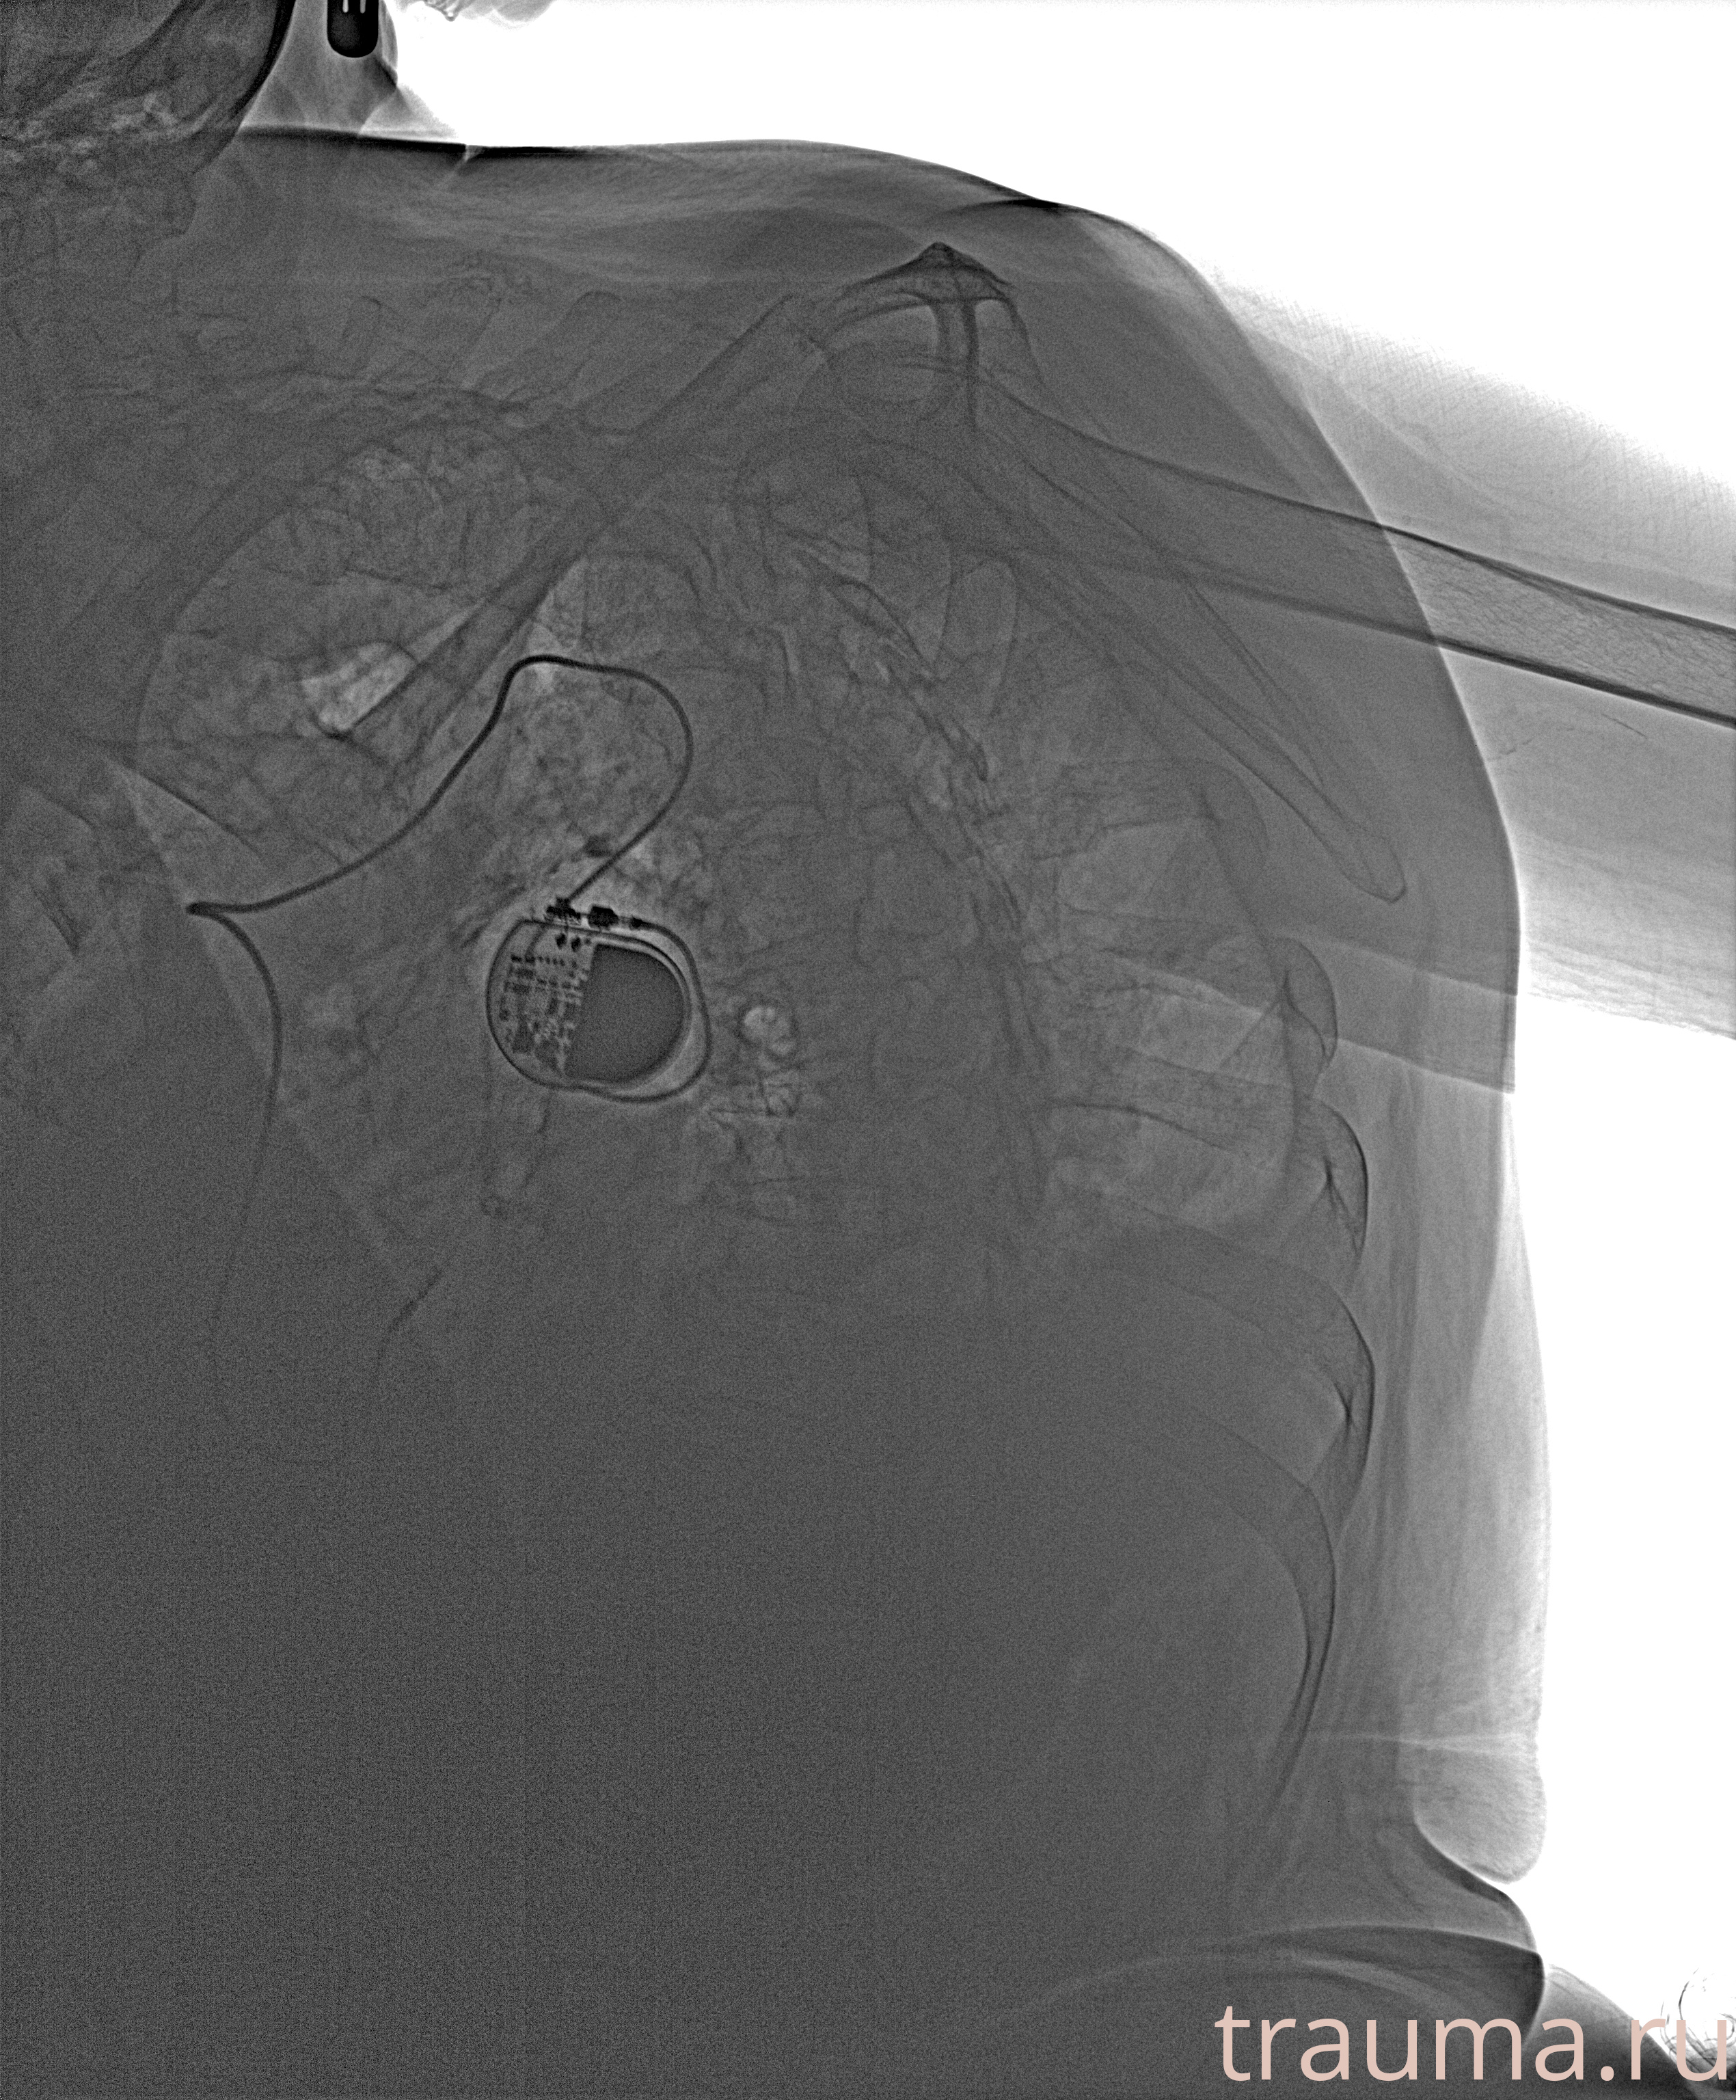

Рентгенограммы

Рентген на дому: по вашему адресу приезжает врач-рентгенолог, травматолог-ортопед с мобильным рентгеновским аппаратом, проводит диагностику травмы или заболевания, делает необходимые рентгенограммы, дает рекомендации по дальнейшему лечению. Получить качественные снимки в домашних условиях возможно благодаря уникальной методике, разработанной МосРентген Центром для института  Склифосовского

при переломе шейки бедра и пневмонии от компании МосРентген Центр - партнера Института имени Склифосовского